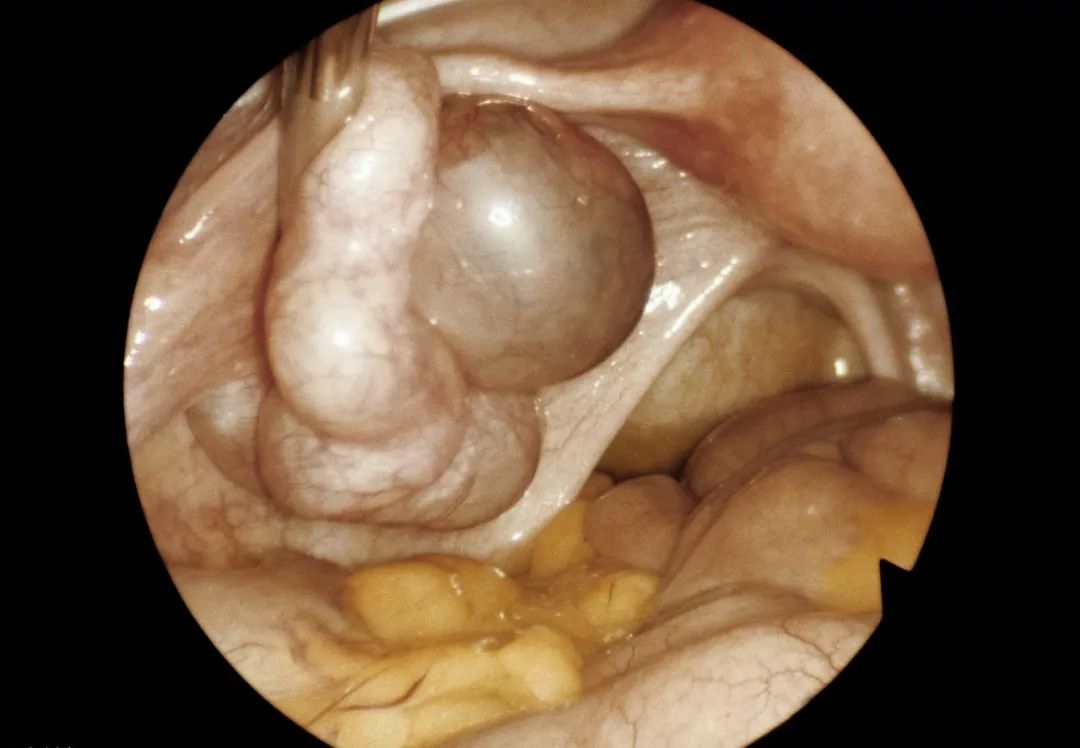

例如,较大的子宫肌瘤或子宫角肌瘤阻塞了输卵管的开口; 或恶性病变直接侵犯输卵管,造成输卵管阻塞或功能损害,导致输卵管不孕。